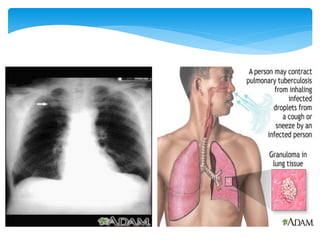

Pulmonary Tuberculosis : Pneumonia caused by

the bacteria Mycobacterium tuberculosis

Pulmonary Tuberculosis :Pneumonia caused by the bacteria Mycobacterium tuberculosis